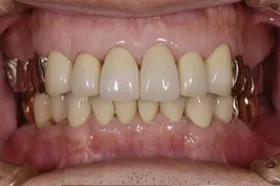

金属を白くし、歯茎の黒ズミを改善したケース

■治療前

■治療後

| 主訴 | 全体的に白い歯にして見た目をきれいにしたい 歯茎が黒くなっているのが気になる、歯ならびも良くしたい |

|---|---|

| 治療方法 | 矯正治療+歯茎の黒ずみの改善+補綴治療 |

| 治療期間 | 3年 |

| 通院回数等 | 約40回 |

| 費用 | 約350万円 |

| リスク・副作用 | 矯正治療も行ったので治療期間が長くなった |